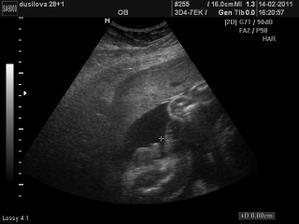

Ve 28tt nám paní doktorka na 3D ukázala krásnýho chlapečka i s jeho pýchou 🙂 Na 99,9% čekáme chlapečka - Tadeáška. Jsem hrozně moc šťastná, že nám vyšlo to co jsme od začátku chtěli - mít starší dcerku a mladšího syna! Tak teď už to jen zdárně doklepat do konce 😀